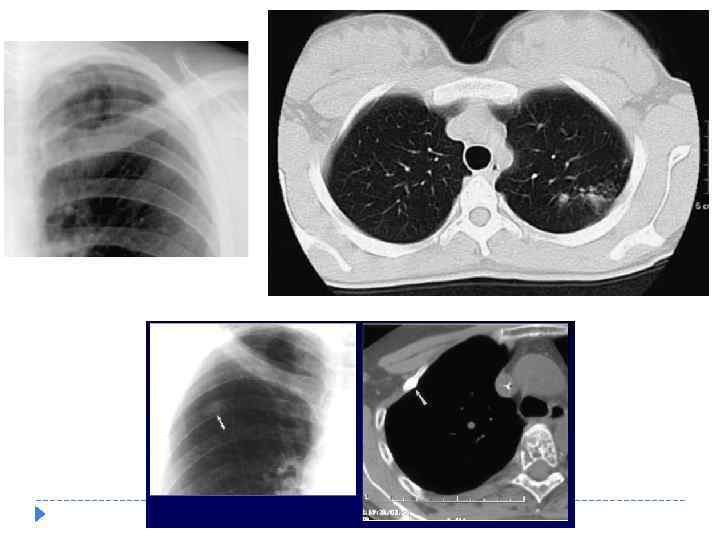

Рентгенологическая характеристика (ОТЛ) Основной рентгенологический синдром: очаги и очаговая диссеминация в лёгочном поле диаметр очага составляет менее 12 мм. - экссудативные (неправильной формы, средних и крупных размеров 7 -12 мм. , с нечеткими контурами за счет перифокального воспаления) - продуктивные (округлой формы, средних размеров 3 -6 мм. , с четкими контурами)

Рентгенологическая характеристика (ОТЛ) Основной рентгенологический синдром: очаги и очаговая диссеминация в лёгочном поле диаметр очага составляет менее 12 мм. - экссудативные (неправильной формы, средних и крупных размеров 7 -12 мм. , с нечеткими контурами за счет перифокального воспаления) - продуктивные (округлой формы, средних размеров 3 -6 мм. , с четкими контурами)

Рентгенологическая характеристика ОТЛ при КТ исследовании Детально оценить характер изменений и констатировать наличие очагов Выявить мелкие полости распада Более достоверно оценить активность очагового туберкулёза

Рентгенологическая характеристика ОТЛ при КТ исследовании Детально оценить характер изменений и констатировать наличие очагов Выявить мелкие полости распада Более достоверно оценить активность очагового туберкулёза